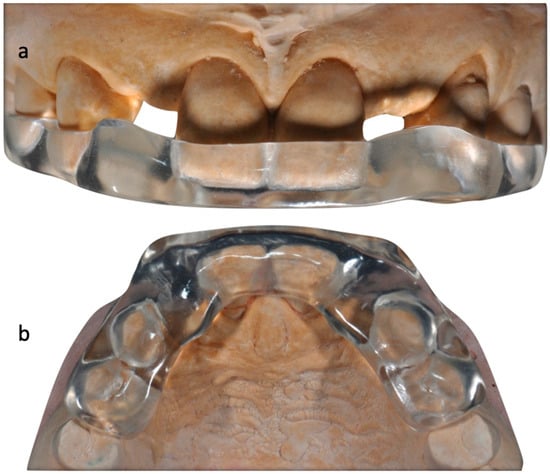

The case describes rehabilitating two congenitally missing lateral incisors in a young patient (38 years old) undergoing orthodontic treatment to create the necessary space for implant placement (Figure 1 and Figure 2). Two fibre-reinforced composite Maryland bridges (Tender Fiber Quattro—Micerium) were utilised for provisional rehabilitation (Figure 3, Figure 4 and Figure 5). Two Osstem TSIII 3.5 × 10.0 implants (1.5 mm subcrestal), two straight Osstem Zirconia abutments, and two-layered lithium disilicate crowns were employed for the definitive restoration (Figure 5, Figure 6, Figure 7, Figure 8, Figure 9, Figure 10, Figure 11, Figure 12, Figure 13, Figure 14, Figure 15, Figure 16, Figure 17, Figure 18, Figure 19 and Figure 20) [,]. The dental implant position was planned after a three-dimensional radiographic analysis in a prosthetically guided way. Patient rehabilitation was performed with an immediate post-surgery provisional (Maryland-type, cemented with a resinous cement) application. Subsequently, a delayed loading of the new provisional dental implant was retained (cemented with zinc oxide eugenol cement) and finally, definitive crowns (cemented with a definitive resinous cement) on Osstem® abutments were installed (3 months).

Figure 3. Initial model and diagnostic wax-up (impression in Zhermack HD silicone with closed tray technique).

Figure 4. Provisional restorations (acrylic resin jet kit).

Figure 6. Transfer key (transparent resin). (a,b) Frontal and occlusal views, respectively.

Initial models and diagnostic wax-ups were created using silicone (Elite HD+, Zhermack) with a closed tray technique, and provisional restorations were fabricated using different colours of acrylic resin (Jet Kit®, Lang, IL, USA). Temporary restorations were then placed in position (Figure 5). A transparent resin transfer key was employed to streamline the implant’s placement. The information regarding the implant’s position was conveyed to the laboratory through a series of specialized steps. These included the installation of titanium temporary abutments sourced from Osstem® in South Korea, securing the workpiece within the transfer key using pattern resin, precision drilling on the master hard stone model (Figure 6, Figure 7 and Figure 8), and an accurate placement of analogues in this model by employing a recasting technique with hard stone material (Figure 9). After revealing the implanted components, provisional restorations were promptly delivered as part of the uncovering procedure to encourage optimal soft tissue healing (Figure 10). Adjustments were made to the emergence profile to condition the surrounding soft tissues properly, and specialized conditioning procedures were carried out (Figure 11 and 12). Before and after conditioning, the changes in the profiles were documented (Figure 13). The new profiles obtained were transferred to the master model by mounting the modified provisional restorations with analogues, and a new artificial gum was created through recasting (Figure 14). Once the soft tissues had healed correctly, guided by the modified and polished provisional as in Figure 11, it was possible to transfer the mucosal profile onto the master model. By removing the provisionals from the oral cavity, they were then positioned on the master model, corresponding to the dental implant analogues in the master model. The master model that had previously been modified and freed from any over contours or undercuts was relined at this point with a laboratory silicone to simulate the profile of the mucosa. The abutments were customised using ceramic and fluorescence techniques to achieve optimal emergence profiles (Figure 15). Gingival profiles were assessed, and the abutments were inserted accordingly (Figure 16 and Figure 17). The final stage involved the placement of crowns, which were fabricated using ceramic material (E.max ceram®, Ivoclar, Naturno, Italy). A last radiographic check was performed to ensure a proper alignment and fit of the restorations. The case was considered completed, and aesthetic integration was achieved. Overall, this case report encompassed various steps, including an initial assessment, diagnostic procedures, provisional restorations, implant placement, emergence profile modifications, abutment customisation, crown placement, and the final evaluation of the completed case.